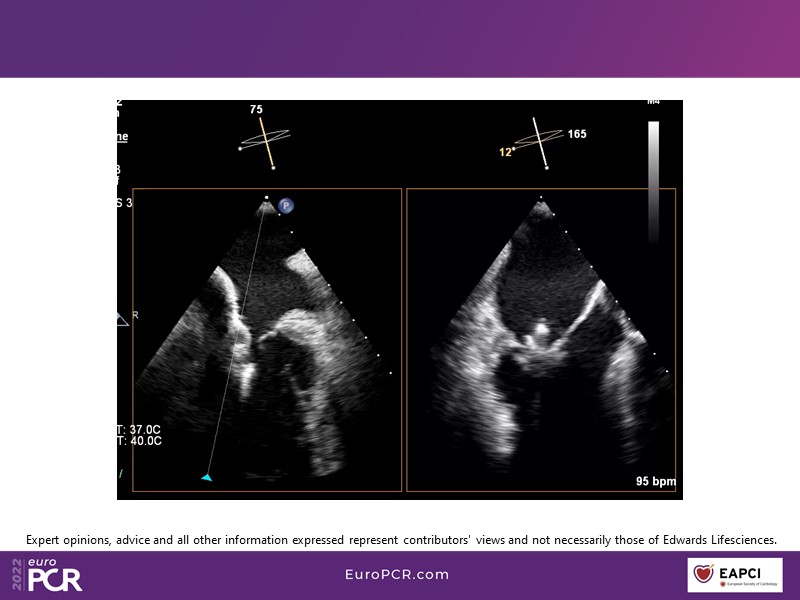

With study outcomes and clinical cases, this EuroPCR 2022 session will enable you to discuss the anatomical considerations that define suitable candidates for treatment of mitral regurgitation with the PASCAL platform and highlight key differentiators and tips and tricks for its use.

- To discuss which anatomical considerations define suitable candidates for the treatment of mitral regurgitation with the PASCAL platform

- To attend case-based discussions that will highlight key differentiators and tips and tricks when using the PASCAL platform to treat mitral regurgitation